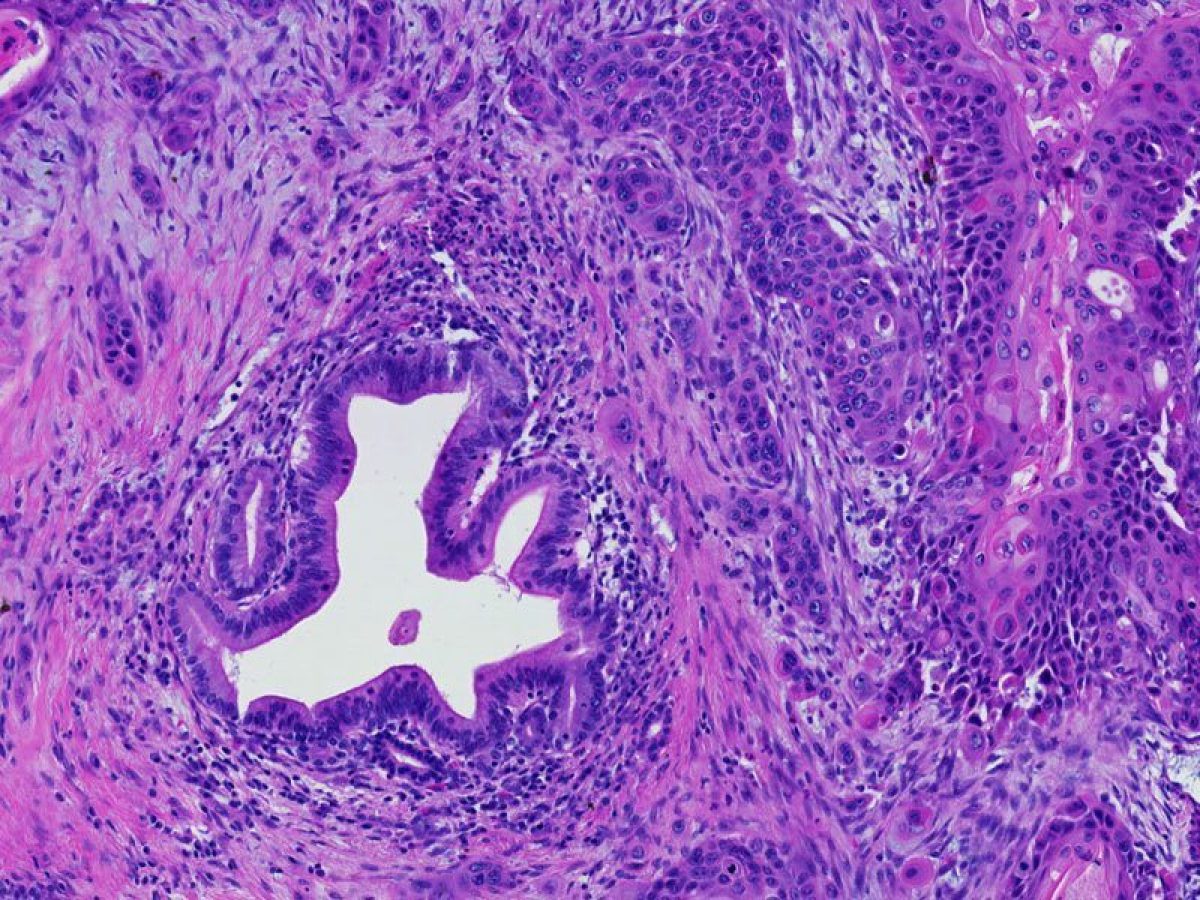

A medical doctor specially trained to study disease processes. Pathologists make the microscopic diagnosis that is used to establish the diagnosis of cancer.

A term used to describe certain tumors which grow in finger-like projections. Pathologists use this term to describe some precancerous lesions in the pancreas (intraductal papillary mucinous neoplasm).

The form of cancer that most people are talking about when they refer to "cancer of the pancreas." These tumors account for 75% of all pancreas cancers.

Microscopically, adenocarcinomas form glands. These tumors can grow large enough to invade nerves which can cause back pain. They also frequently spread (metastasize) to the liver or lymph nodes. If this happens the tumor may be considered unresectable.